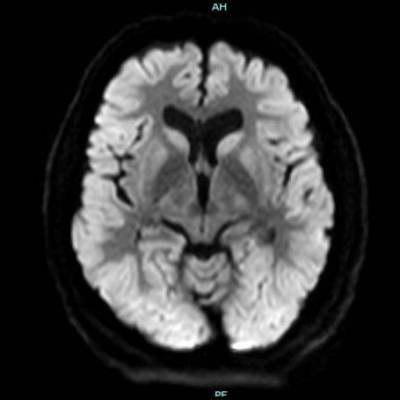

- A) Bilateral serebral kortekste (oklar) ve bazal ganglionlarda (oklar) yaygın DAG hiperintens, ADC hipointens difüzyon kısıtlamaları görülüyor.